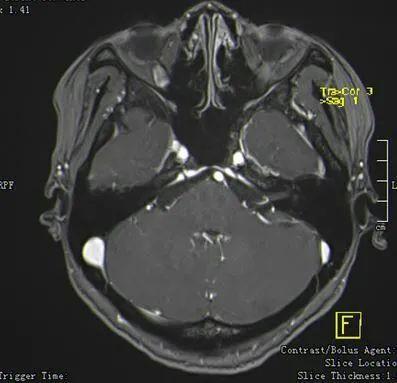

第三例舌咽神经痛王某,女,52岁,“右侧阵发性咽后壁疼痛一月余”入院

舌咽神经痛与右侧小脑后下分支血管关系紧密

术中暴露神经与血管

游离舌咽神经与迷走神经

电凝舌咽神经支

剪断杜绝后患

术后患者疼痛症状明显缓解,无声音嘶哑,吞咽呛咳等并发症!